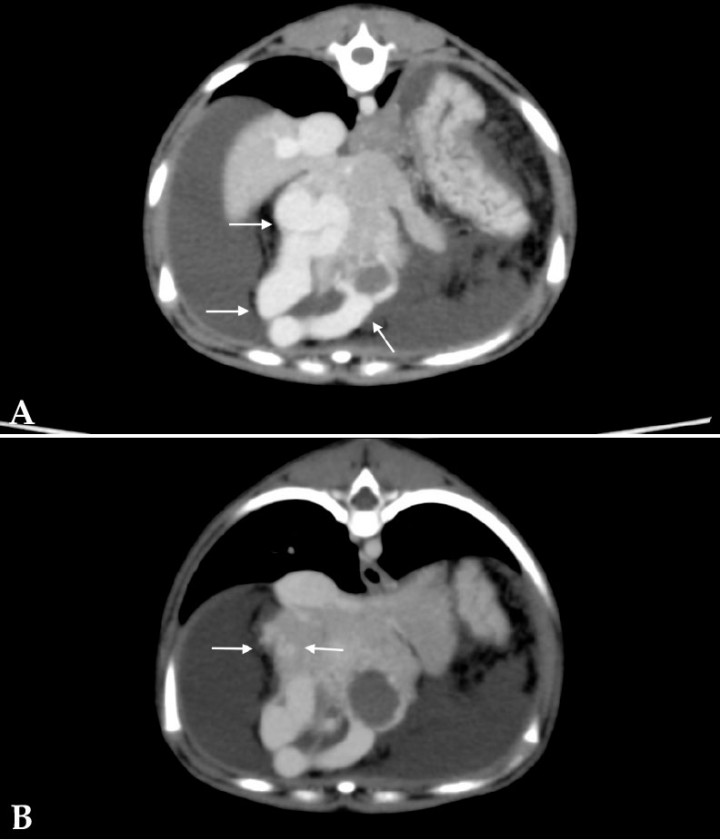

A partir de las ramas de la arteria hepática principal se observó un plexo de vasos tortuosos que desembocaban en dos ramas portales: en una rama intrahepática en el lóbulo medial izquierdo, craneoventral y adyacente al diafragma, resultando en una rama portal anormalmente dilatada y tortuosa (Fig. 7A); y en la propia rama portal tortuosa y aumentada de tamaño a partir de dos arteriolas hepáticas que nacían desde el lado derecho de la arteria hepática (Fig. 7B).

<p>Imágenes de tomografía computarizada transversales tras la administración de contraste intravenoso, ventana de tejido blando. (<strong>A</strong>) Se observa la rama portal intrahepática en lóbulo medial izquierdo anormalmente dilatada y tortuosa (flechas). (<strong>B</strong>) Se aprecian vasos tortuosos (flechas) que drenan en la vena porta tortuosa y aumentada de tamaño.</p>

Figura 7

Imágenes de tomografía computarizada transversales tras la administración de contraste intravenoso, ventana de tejido blando. (A) Se observa la rama portal intrahepática en lóbulo medial izquierdo anormalmente dilatada y tortuosa (flechas). (B) Se aprecian vasos tortuosos (flechas) que drenan en la vena porta tortuosa y aumentada de tamaño.